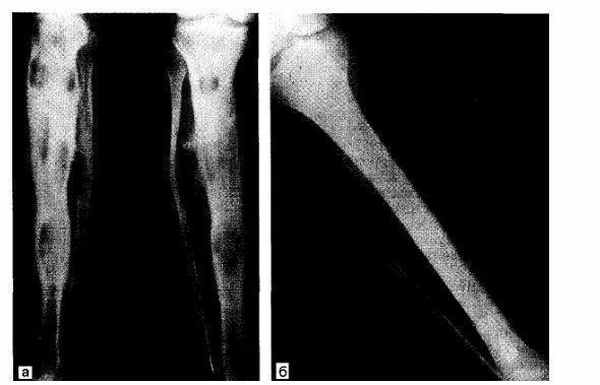

Рис.24.2. Хондросаркома 3 /4 большеберцовой кости. а — удаление здоровых тканей с опухоли по типу «снимания чулка с молнией»; б — замещение дефекта аллотрансплантатом.